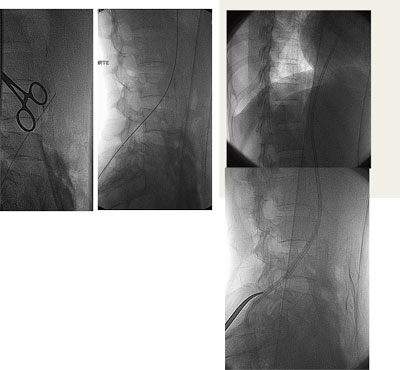

Paciente feminino, 50 anos, portadora de insuficiencia renal terminal em tratamento em outra instituição, já com fibrose peritoneal e com múltiplas confecções de fístulas arteriovenosas nos membros superiores sendo a última fístula um enxerto bráquio-jugular direito pois a paciente apresentava oclusão das veias subclávias. Tal enxerto arteriovenoso havia trombosado há 5 dias e não ocorreu sucesso na tentativa de trombectomia cirúrgica. Sem realizar diálise a paciente apresentava sinais de uremia (confisão mental e sonolência), anasarca e tinha potássio de 8.0mg/dl quando foi solicitado nossa avaliação nesta outra instituição. Encaminhado a paciente para sala de ultrassonografia onde foi avaliado as veias jugulares, subclávias e femorais, todas mostraram-se ocluídas. Em virtude da urgência dialítica foi implantado um cateter de duplo lúmen na veia poplítea direita guiado por ultrassonografia. Foi realizado hemodiálise por três dias consecutivos, sendo alcançado fluxo de 150 ml/min. Houve melhora clínica e dos níveis urêmicos e de potássio. A paciente foi então transferida para nossa instituição onde foi submetida à flebografia dos membros superiores, não ocorrendo opacificação das veias axilares, subclávias e veia cava superior. Realizado tentativa de recanalizacão da veia femoral direita sem sucesso. Optado pelo implante translombar de cateter de duplo lúmen tipo permcath. O procedimento transcorreu sem intercorrências e a paciente teve alta no dia seguinte. Após 9 meses de acompanhamento a paciente apresentou infecção do cateter sendo trocado por um novo cateter via translombar.